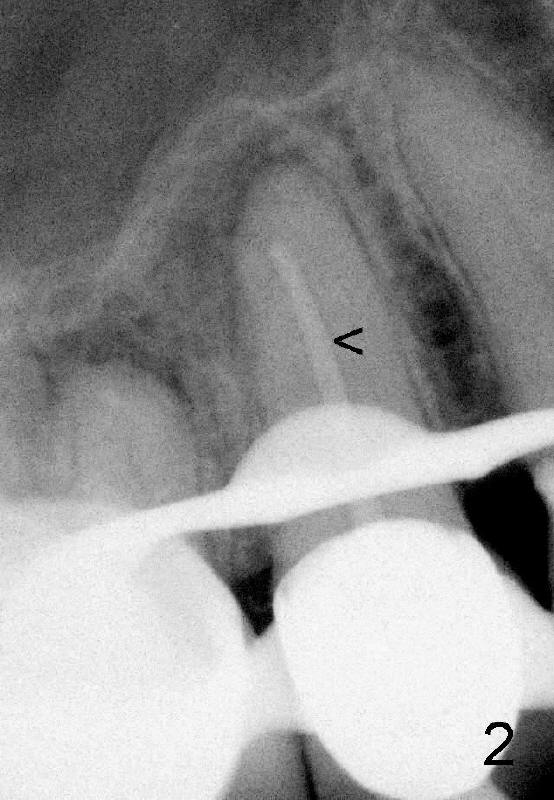

四十八岁俄国女人去年因右上牙痛就诊,右上五(图一:美国称为四号牙)有牙冠修复,叩诊疼痛,牙髓测定死髓牙,术前很难理解为什么根管末端弯曲(图一':红箭头;白箭头代表根尖阴影范围),根管扩大至40/.06(rotary file),插入同一号牙胶尖(图二箭头),好像挺接近弯曲根管顶端,但是离根尖还有一些距离,从牙冠打洞,里面一片漆黑,使用两倍半放大镜(loops),也无能为力,最后完成根管充填(图三),看上去挺不错,顺着弯曲根管走(箭头),有些得意洋洋,最末端部分(上下箭头之间)可能被糊剂充填。欣慰的是术后疼痛消失,一年后病人因右下桥松动而再次就诊,检查表明七断裂需要拔牙,植牙,由于下牙槽神经在根尖片中看得不清楚,她牙齿问题很多,便拍摄全口CT。右上五CT显示根尖阴影好像没有减少多少(图四箭头,与图一',图二,图三对比),所以根管末端弯曲有一定特殊意义,那是什么呢?